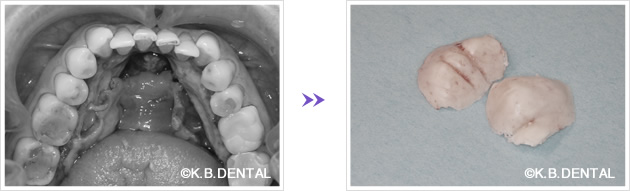

口蓋隆起 症例2

口蓋隆起 症例3

歯の内側に発生したタイプの骨隆起です。静脈麻酔で約1時間半程度要します。

口蓋隆起 症例4(正中口蓋隆起)

口蓋の正中に発生した骨隆起です。静脈麻酔で約1時間半程度要します。